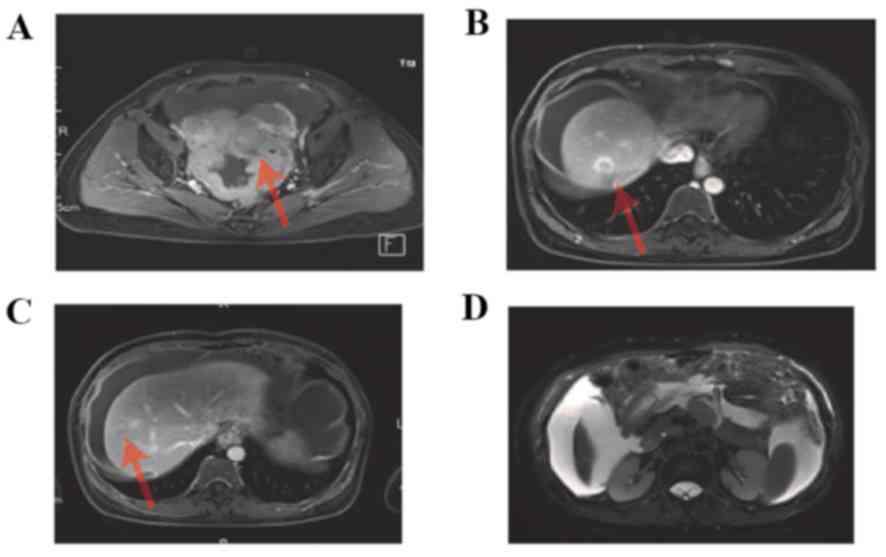

2J-L). An MRI scan was performed, which demonstrated

enhancement of the pelvic tumor (Fig.

3A), enhancement of hepatic metastasis (Fig. 3B,C), and thickening of the omentum

majus and tumor tissue (Fig. 3D).